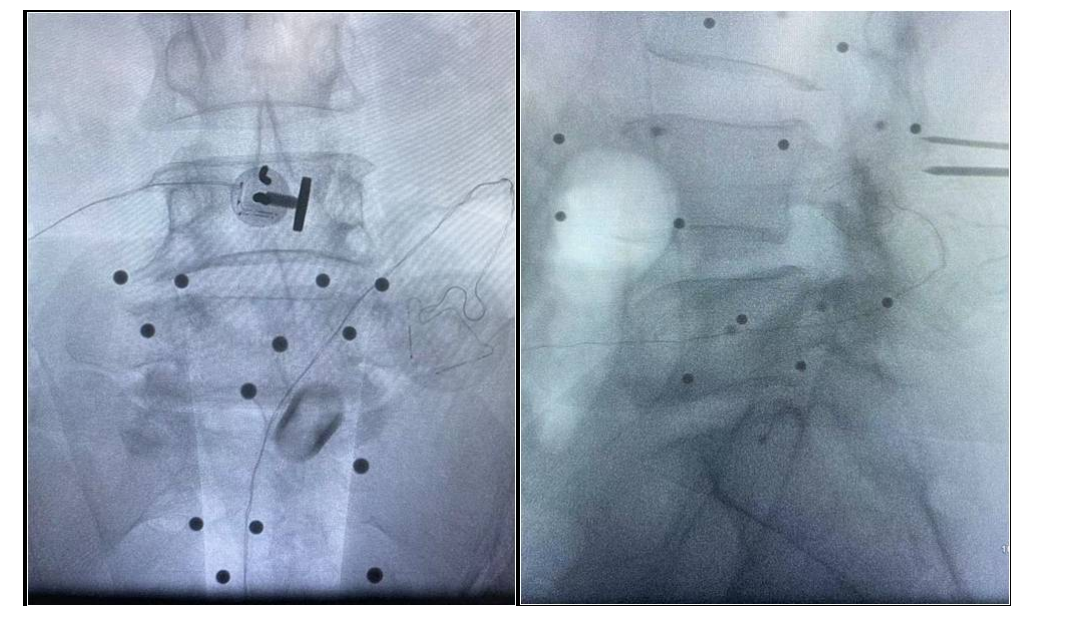

腰椎滑脱微创融合病历4

吕X,女,56岁。

主诉:腰疼及双下肢疼痛麻木伴活动受限3年加重半年。

查体:L4-5棘间及椎旁压痛,右下肢直腿抬高试验60°阳性,左下肢50°阳性,双下肢肌力肌张力正常。